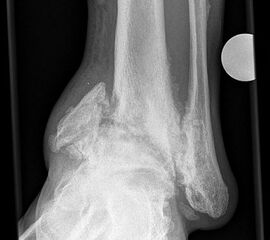

Abbildung 2

DNOAP Typ I (Abb. 2):

Hierbei handelt es sich um Nekrosen der Interphalangeal-, Metatatarsophalangealgelenke und Metatarsalia, was es zur knöchernen Resorption an den Mittelfußköpfchen und Zehengliedern führt. Die Stummel der Metatarsalia gleichen abgelutschten Zuckerstengeln, bohren sich in der Abstoßphase in die Sohle und führen zum Malum perforans.